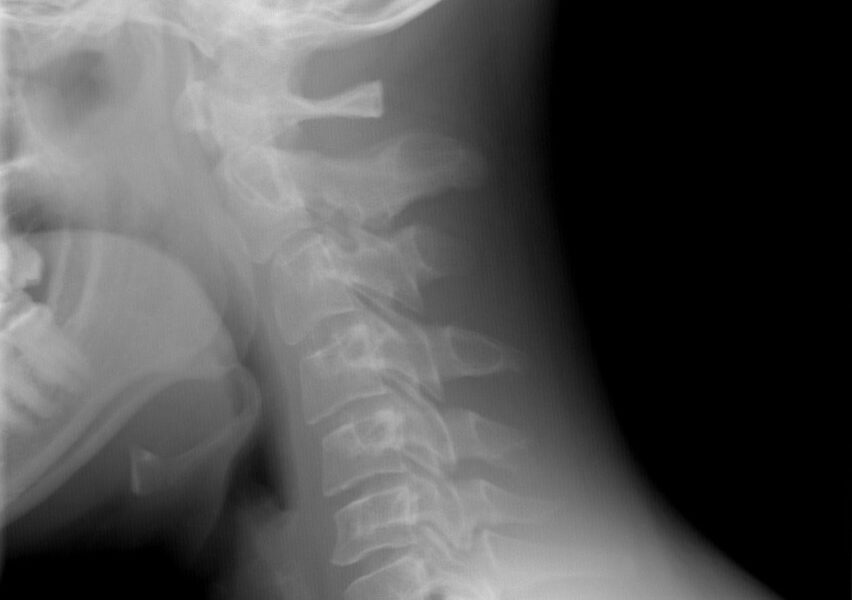

La rectificación de la lordosis cervical es el aplanamiento de esta curva. Las curvas de la columna no están de más, nada lo está en el cuerpo. Aumentan la protección de la misma ante impactos y protege a la médula y los discos intervertebrales. La inversión de la lordosis es el paso siguiente y es cuando se crea la curva contraria.. Por todo ello, resulta fundamental el tratamiento de la rectificación. Al tratarse de una alteración estructural, el abordaje será a través de la terapia manual (fisioterapia). Y el objetivo del tratamiento será reconstituir la lordosis fisiológica (curvatura normal) de la columna cervical. Hay tres pases obligatorios para trabajar una.